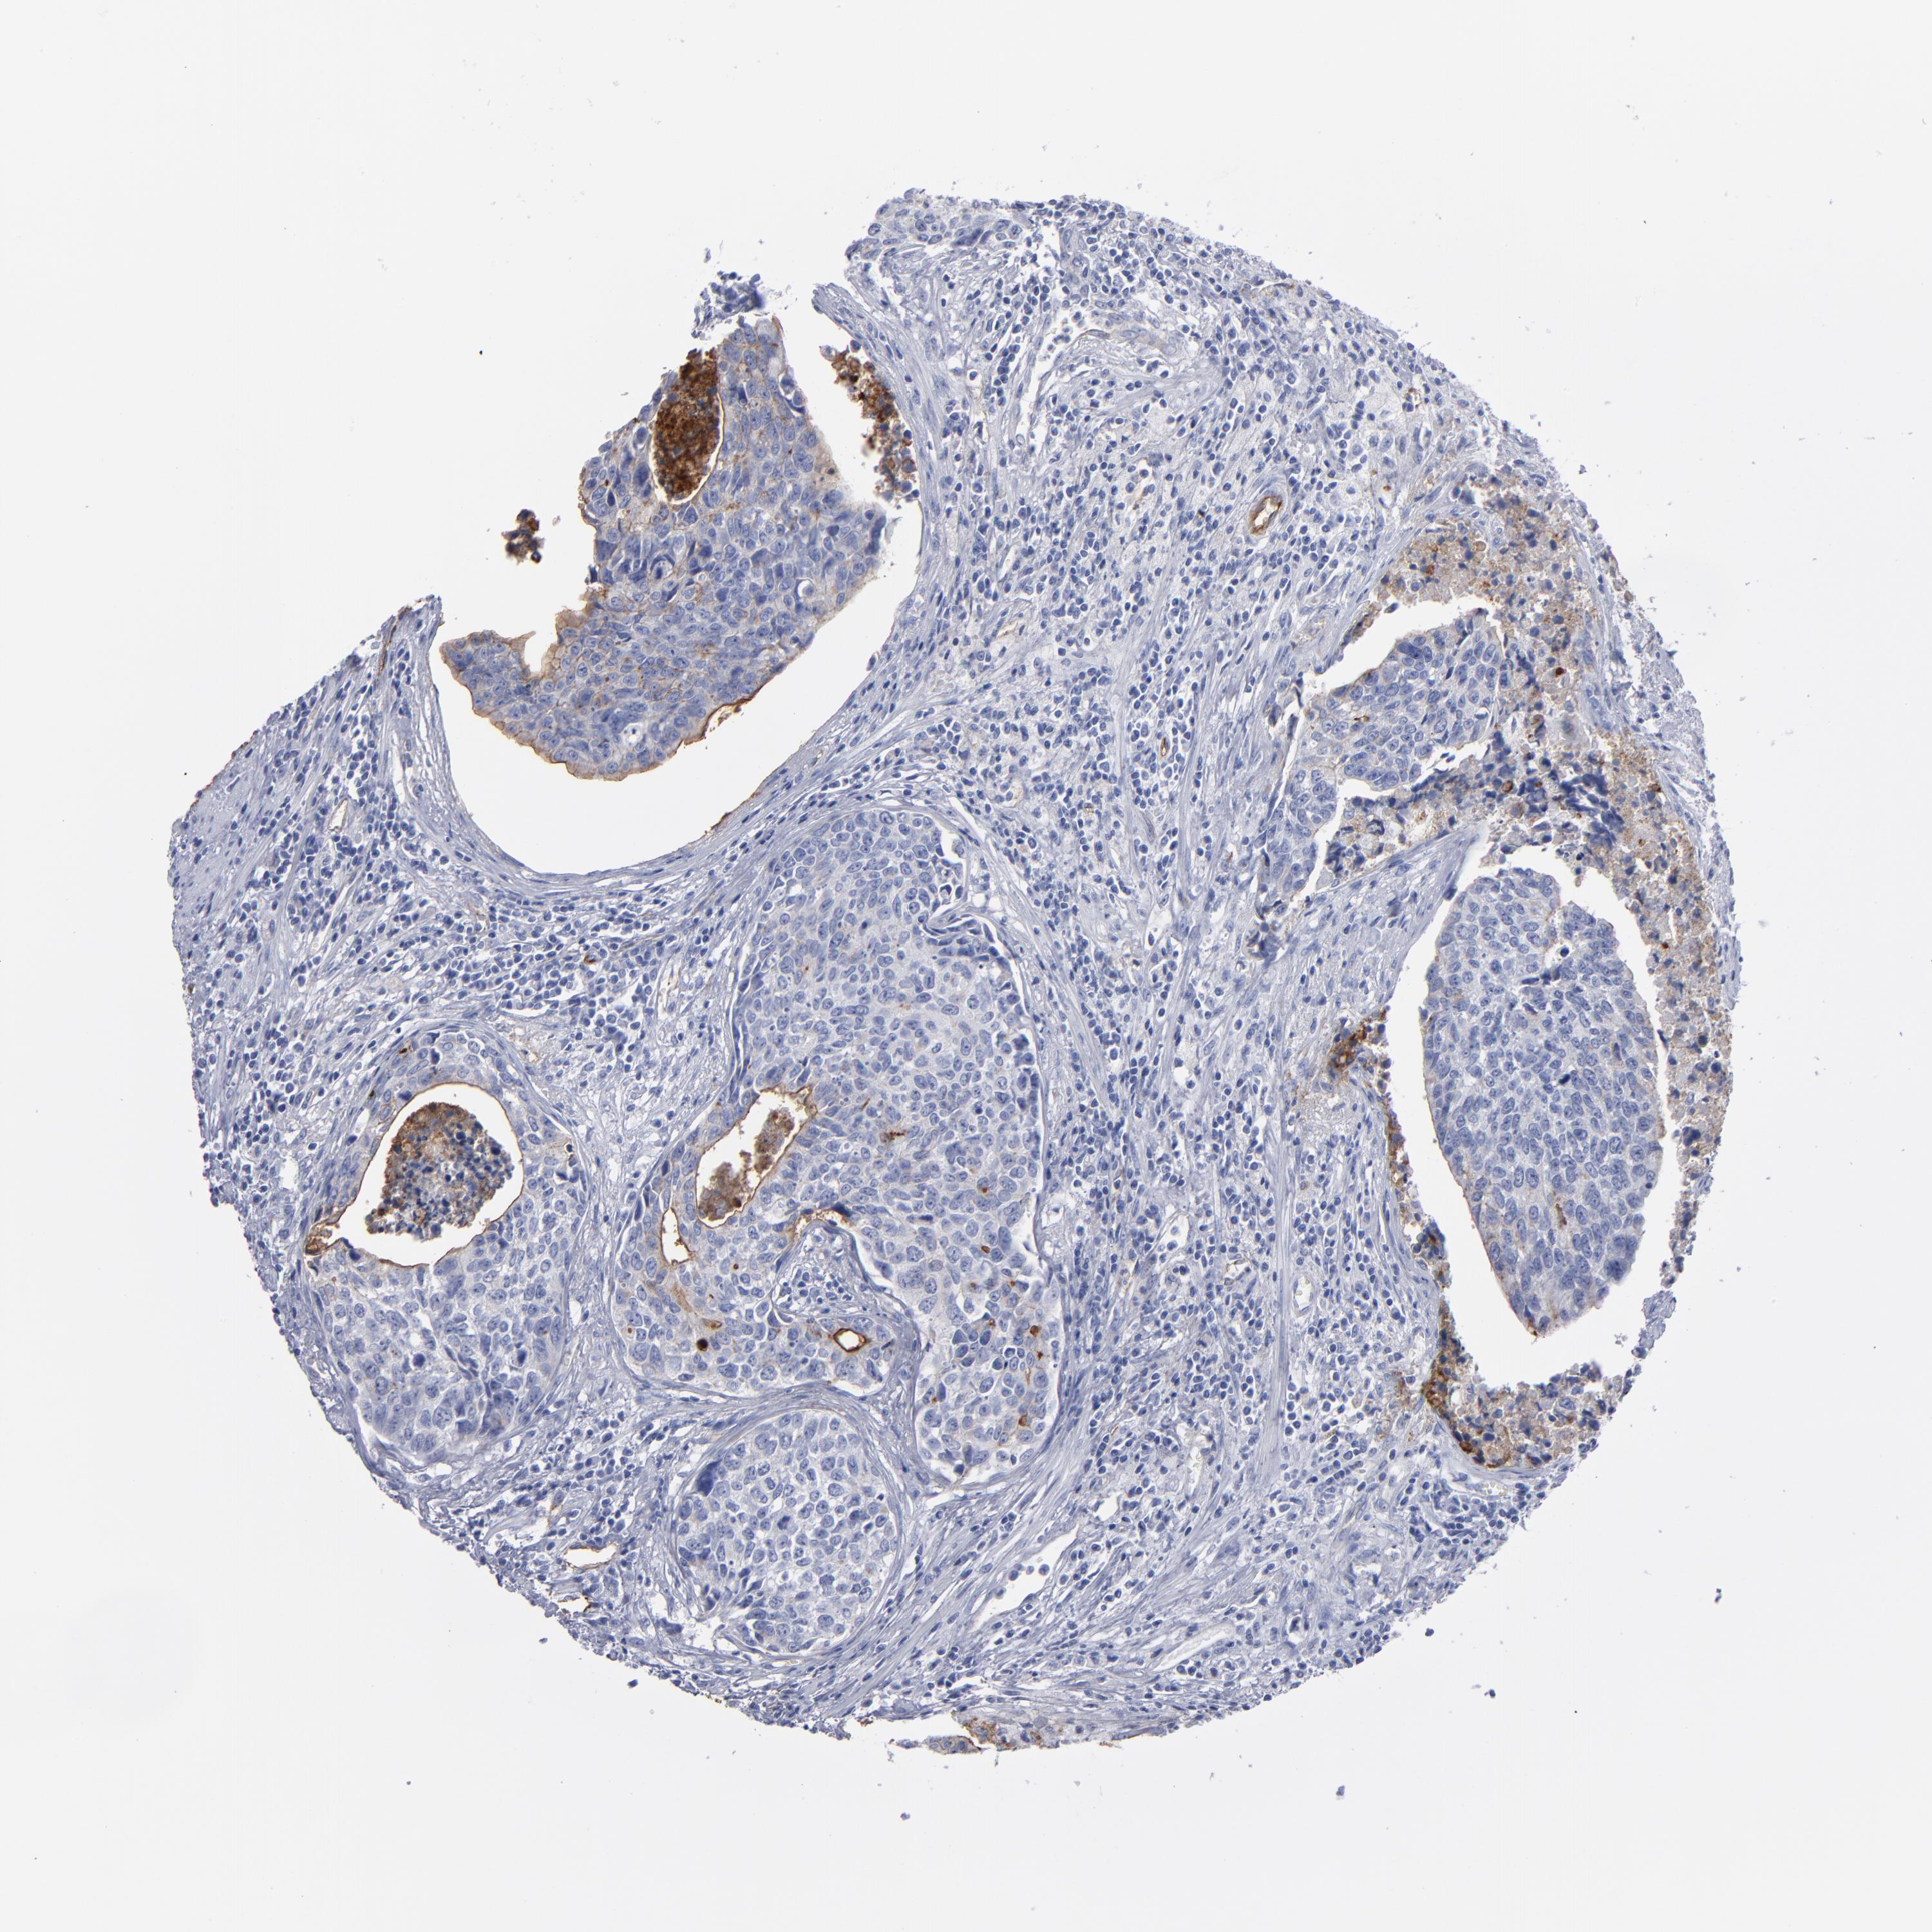

UROTHELIAL CANCER - Protein expressioni

A mouse-over function shows sample information and annotation data. Click on an image to view it in a full screen mode. Samples can be filtered based on level of antibody staining by selecting one or several of the following categories: high, medium, low and not detected. The assay and annotation is described here.

Antibody stainingi

Antibody staining in the annotated cell types in the current human tissue is reported as not detected, low, medium, or high, based on conventional immunohistochemistry profiling in selected tissues. This score is based on the combination of the staining intensity and fraction of stained cells.

Each image is clickable and will lead to virtual microscopy that enables deeper exploration of all samples and also displays staining intensity scores, fraction scores and subcellular localization as well as patient and tissue information for each sample.

Antibody HPA002823

Antibody CAB002760

Staining

High

Medium

Low

Not detected

Intensity

Strong

Moderate

Weak

Negative

Quantity

>75%

75%-25%

<25%

None

Location

Nuclear

Cytoplasmic/membranous

Cytoplasmic/membranous,nuclear

Urothelial carcinoma, Low grade